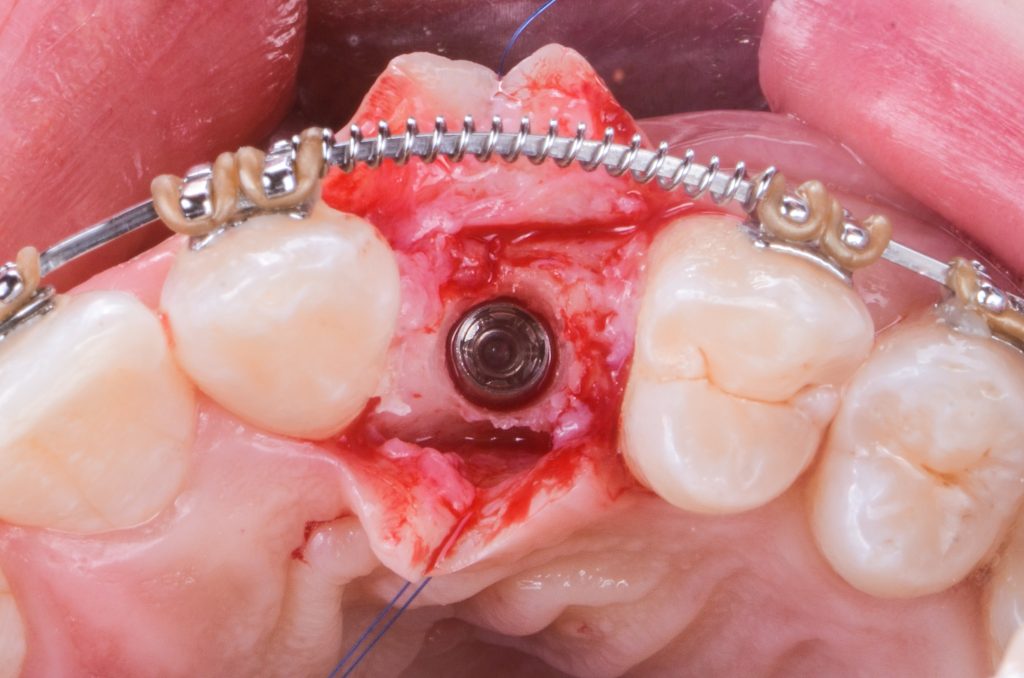

sufficient bone width in cuspid area

the sliding island flap secured with 6/0 stitches